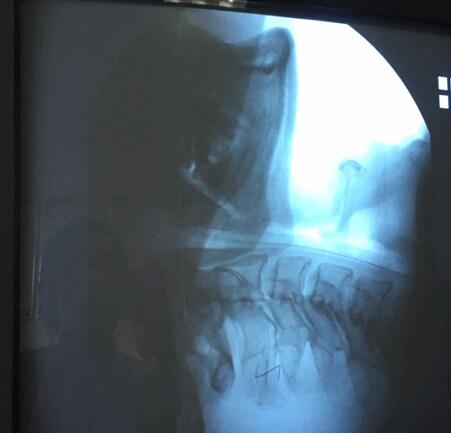

吞咽造影檢查,是在X線透視下,針對(duì)口、咽、食管的吞咽運(yùn)動(dòng)所進(jìn)行的特殊造影,此項(xiàng)檢查可以進(jìn)行點(diǎn)片或錄像來記錄所看到的影響,并加以分析。通過吞咽造影檢查,臨床上可以明確患者是否存在吞咽障礙,可以發(fā)現(xiàn)吞咽障礙的結(jié)構(gòu)性或功能性異常的病因及其部位、程度和代償情況,吞咽障礙發(fā)生在哪個(gè)時(shí)期,有無誤吸,尤其是會(huì)并發(fā)肺炎的高度危險(xiǎn)的隱形誤吸,嚴(yán)重程度如何,評(píng)價(jià)代償?shù)挠绊?,為選擇有效治療措施(進(jìn)食姿態(tài)治療和姿勢(shì)治療)和觀察治療效果提供依據(jù)。因此,吞咽造影檢查被認(rèn)為是診斷吞咽障礙首選和理想的方法,常被認(rèn)為是評(píng)價(jià)吞咽障礙的“金標(biāo)準(zhǔn)”,對(duì)指導(dǎo)臨床吞咽治療工作具有重要意義。

該患者于6月23日在山東濰坊因腦干梗死出現(xiàn)吞咽功能減退,并在當(dāng)?shù)匾患裔t(yī)院進(jìn)行檢查與治療,之后轉(zhuǎn)入我院進(jìn)行診治,經(jīng)過詳細(xì)的資料查詢和反復(fù)思索,我院康復(fù)醫(yī)學(xué)科責(zé)任總治療師梁莉娜大膽提出開展吞咽造影檢查的設(shè)想,隨即與介入導(dǎo)管室積極協(xié)調(diào),制定了詳細(xì)的實(shí)施方案,于7月14日順利完成檢查。最終,初步檢查造影結(jié)果為吞咽障礙(咽期)、誤吸、環(huán)咽肌不完全開放。